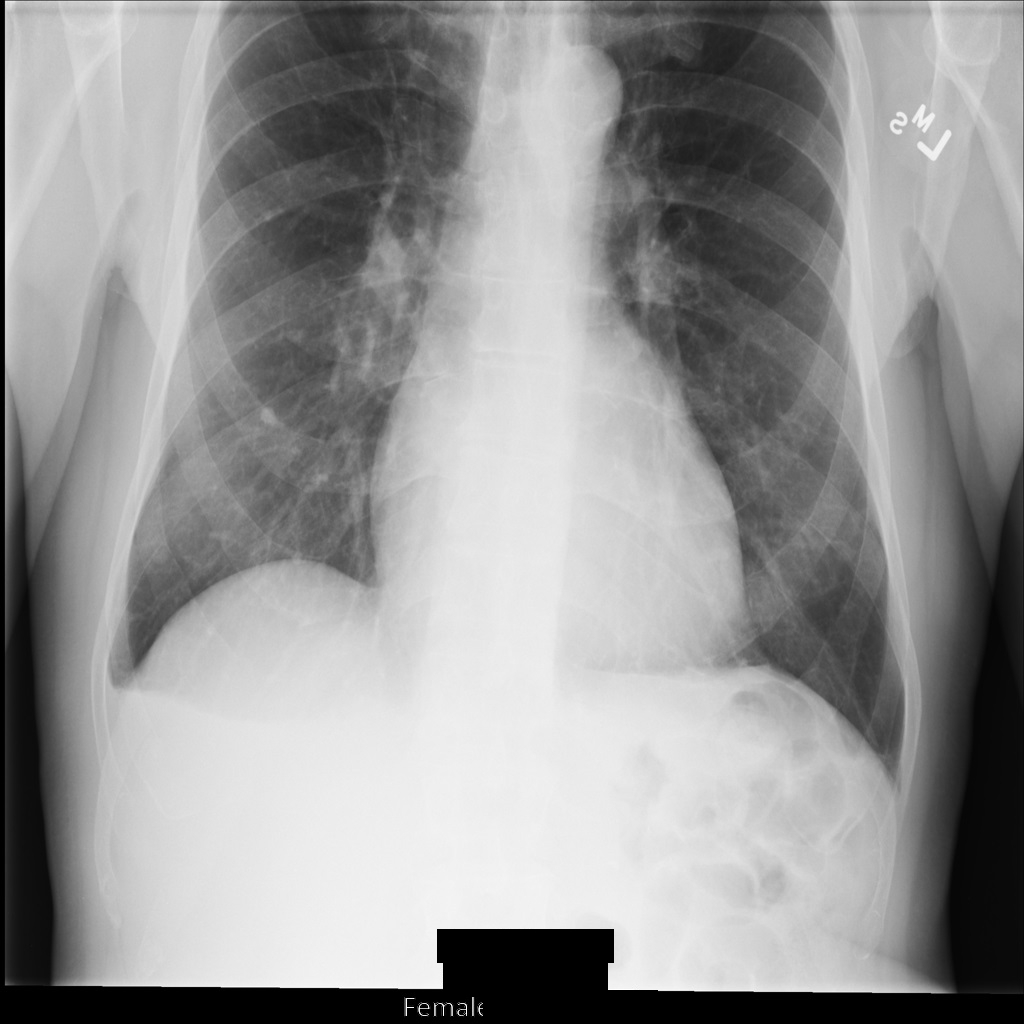

The following sections show what the image in the DICOM instance looks like and the metadata in the instance.

Sample image

Some samples in this page contain an output of the de-identified image. Each sample uses the following original image as its input. You can compare the output image from each de-identification operation to this original image to see the effects of the operation: